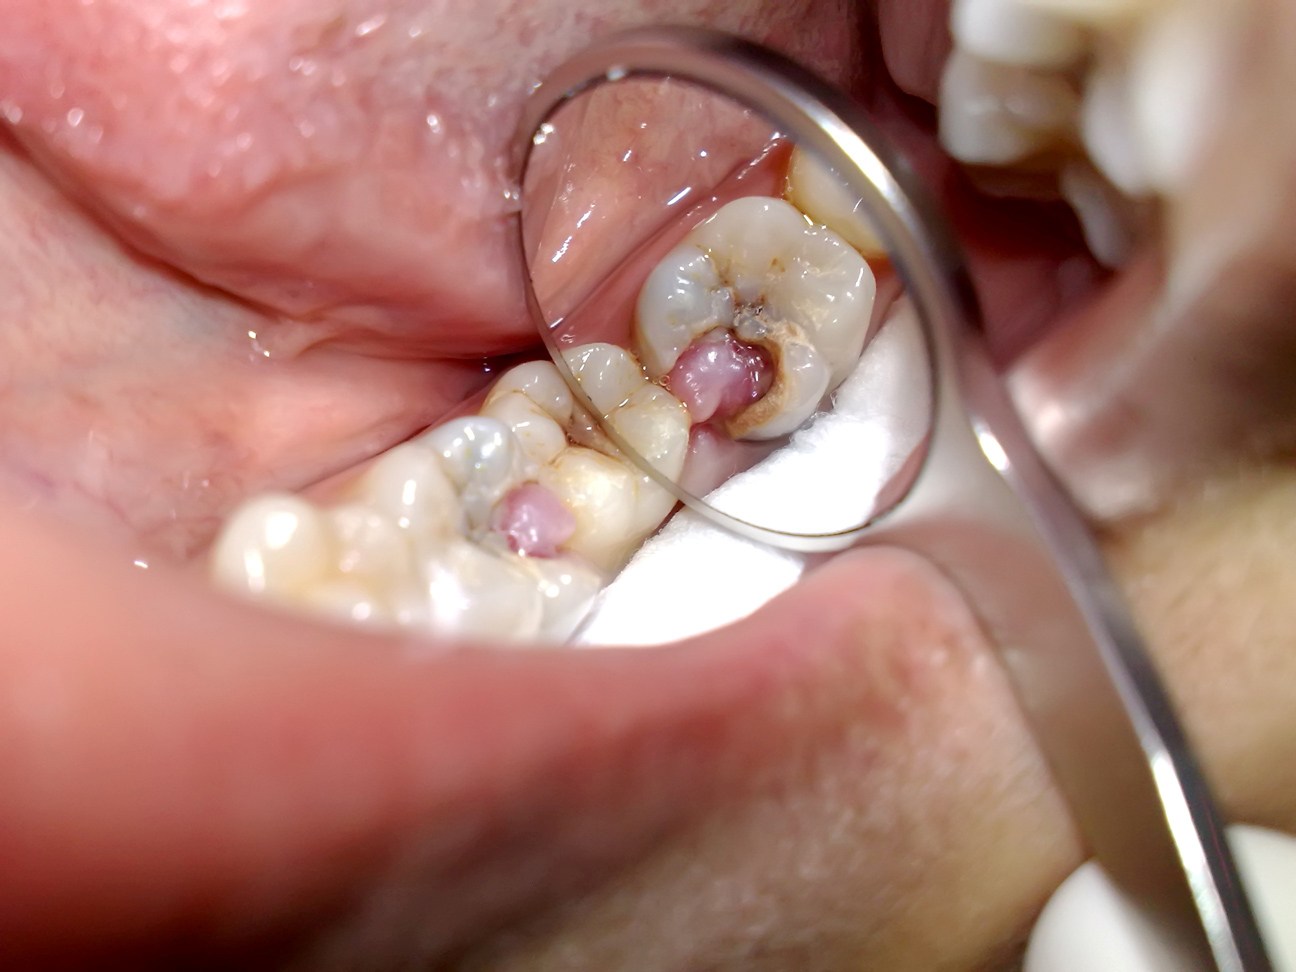

3- Potofu: Njia ya uhakika ya kutibu jino ni kuling’oa.

Ukweli: Ziko njia nyingi na za uhakika za kutibu jino bila kung’oa. Kung’oa jino kama tiba ni pale tu ambapo jino hilo haliwezi tibika kwa njia yoyote na kukaa kwake kwaweza kuleta madhara zaidi. Kung’oa jino huleta madhara mengine na meno bandia pamoja na kwamba hayawezi kurejesha kazi za meno yaliyong’olewa kwa kiwango halisi, lakini pia utunzaji wake ni mgumu na gharama pia.

Hata hivyo, kama umelazimika kupoteza meno basi meno bandia ndilo chaguo pekee.